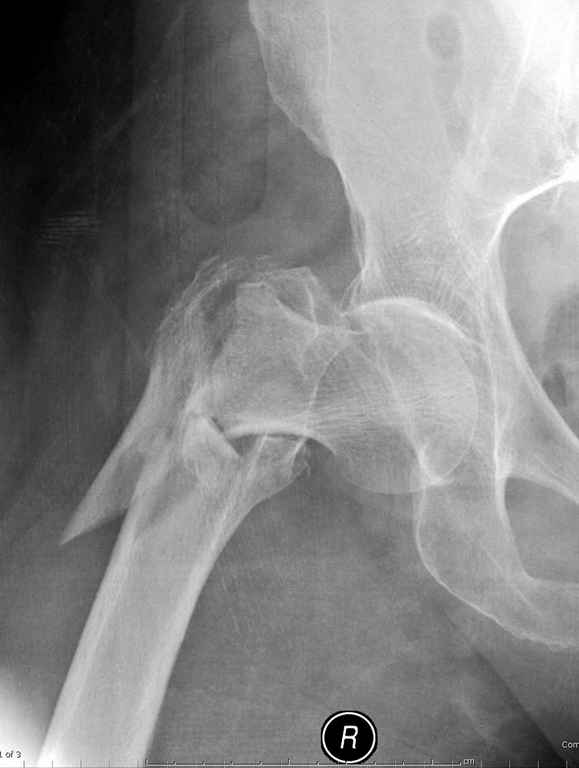

Re: оскольчатый чрезвертельный перелом

А что тут заставляет сомневаться? Здесь настолько очевидно предпочтителен закрытый интрамедуллярный остеосинтез реконструкционным стержнем (проксимальные гвозди толстоваты для такого молодого возраста), что закрадывается мысь о каком-то подвохе.

Желательно бы и снимок бедра на протяжении и в другой проекции.

Не солидно экономить на пленке, это не делает чести презентации. Такие ограниченные нестандартные снимки приводят к тактическим ошибкам.

Предугадать распространение линий перелома при чрезвертельных и оскольчатых переломах трудно, поэтому для принятия правильного решения рекомендуется Компьютерно Томографические исследование.

При отсутствии КТ, снимок на вытяжении поможет увидеть общую картину расположения отломков, особенно потенциальные места введения импланта. Риск раскола в этом случае огромный, поэтому больной должен быть дообследован.